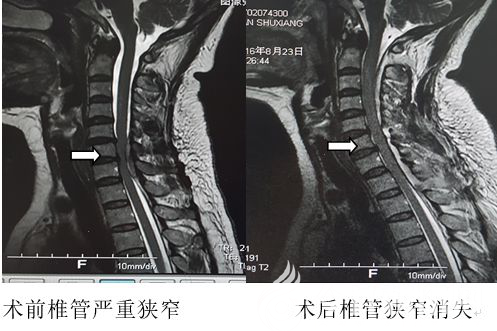

患者50歲,女性,家住遼寧省北票市,因“突發(fā)四肢麻木伴步態(tài)不穩(wěn)4天”前來(lái)該院門診,以脊髓病變性質(zhì)待查入住該院神經(jīng)內(nèi)科。入院后,下肢無(wú)力進(jìn)行性加重,肌力二級(jí),不能下地行走。查磁共振平掃提示:頸6-7水平椎管內(nèi)硬脊膜外血腫,繼發(fā)椎管狹窄?;颊咿D(zhuǎn)入神經(jīng)外二科后,張文主任組織討論,考慮血管畸形出血或腫瘤卒中可能性較大,術(shù)前評(píng)估角度需盡快完善磁共振增強(qiáng)檢查。

由于患者截癱進(jìn)展較快,如不能及時(shí)解除脊髓壓迫,可能形成永久性截癱。于是,科室決定急診手術(shù),手術(shù)在全麻下進(jìn)行。術(shù)后病理為血管脂肪瘤卒中,患者下肢肌力迅速恢復(fù),出院時(shí)可下地行走,患者及家屬均露出了久違的笑容。